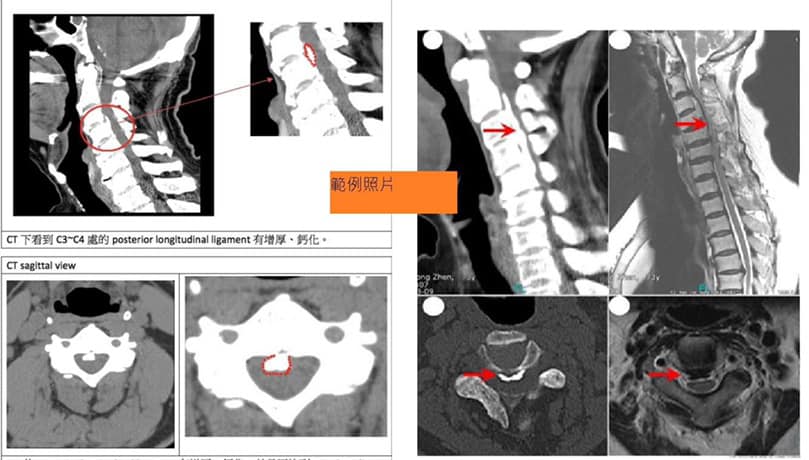

👌評估:後縱韌帶鈣化引起椎管狹窄

🔝首先看卡通圖,此韌帶位於脊椎體的後緣,緊接其後的就是包含有脊髓的椎管。當它過度增生,進而鈣化並骨化,且漸增厚,所占面積增加時,會造成椎管狹窄,嚴重時則壓迫脊髓與神經根,逐漸出現手腳無力麻木等輕重不同的症狀,個案中的姜先生後縱韌帶鈣化非常明顯!